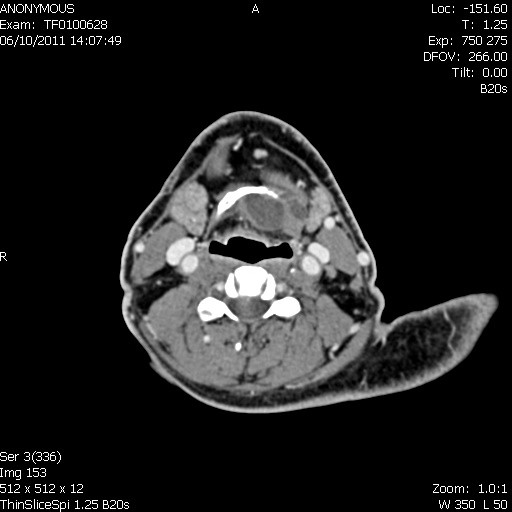

Deep space neck infection